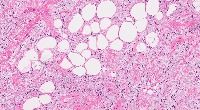

Adipose Tissue

Lipoma